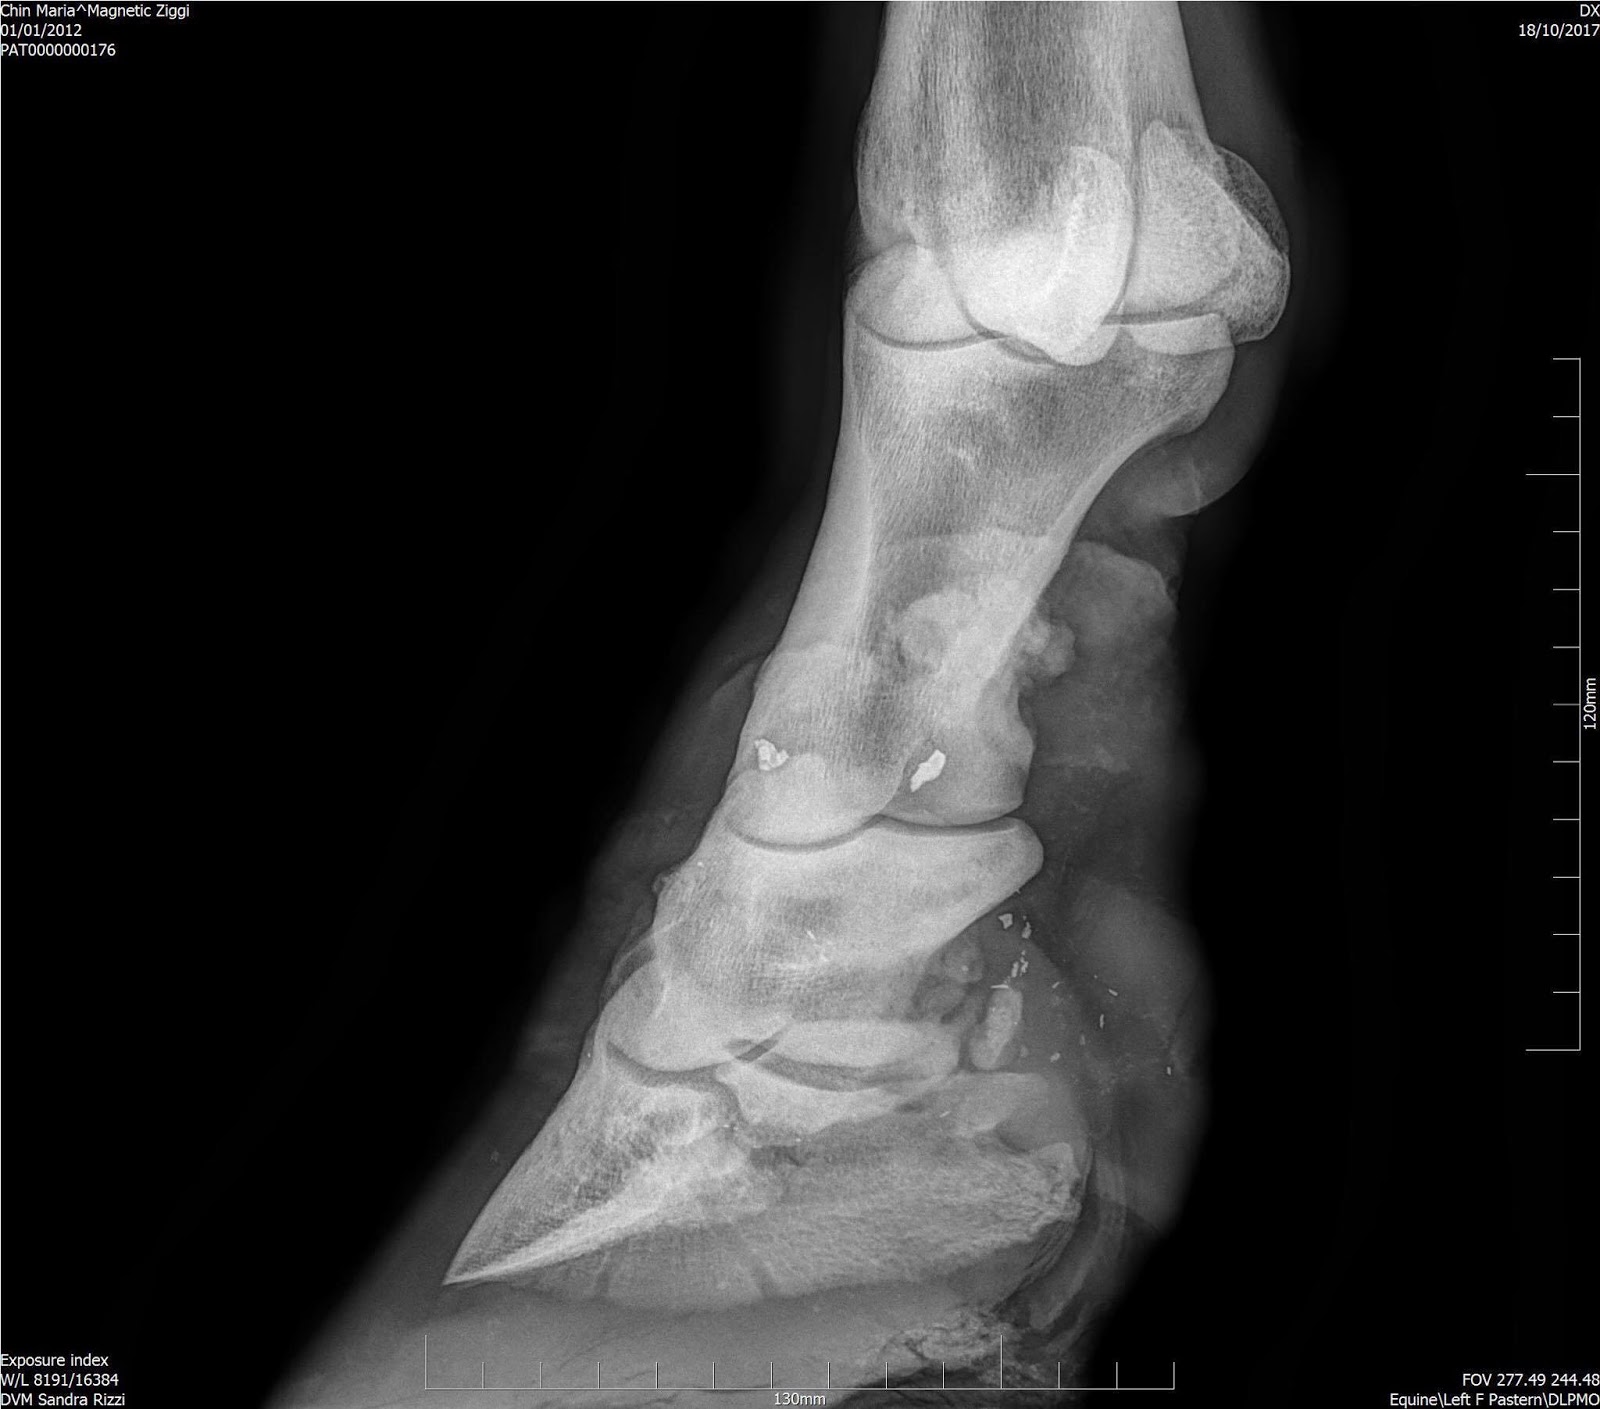

Навикулит и повреждение связок.

До и после

Интересно с навикулитом, челнок же вряд ли восстановится, это ж кость. Я так понимаю, речь идет о связках.

В августе 2018 все три ветеринара поехали в КА9 для осмотра структуры и место где все произошло, по заключению моего ветеринара и ветеринара А был сделан вывод что лошадь не могла травмироваться так сильно в шагалке и что наверняка случилось что-то более серьезное, наличие маленьких кусочков металла в ноге на это указывают.

В октябре 2018 был официально установлен диагноз, но ветеринар А занизил стоимость до 27т евро.

После подтверждения диагноза мы сразу же начали терапию с использованием стволовых клеток.

Дзигги ответил положительно и в этом году мы продолжим.

Дзигги гуляет и чувствует себя намного лучше, благодаря клеточной терапии хромота значительно уменьшилась, а также улучшилось состояние ноги, как будут обстоять дела дальше я не знаю, но то что мы продолжим терапию это однозначно.